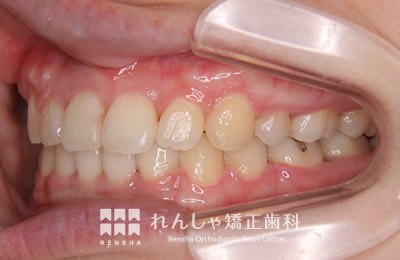

中高生

永久歯列はほぼ完成してしますが、歯列を側方だけでなく後方へも拡大し、埋まっていた右上奥歯を引っ張り出しています。

| 主訴 | 埋まったままでてこない歯がある |

|---|---|

| 診断名 | Angle Class II 小臼歯の埋伏と叢生を伴う上顎前突 |

| 初診時年齢 | 13歳5か月 |

| 装置名 | マルチブラケット装置 |

| 抜歯非抜歯 | 非抜歯 |

| 治療期間 | 2年3か月 |

| 費用の目安 | 約82万円+消費税(検査料金、都度の処置費用等も合わせた総額) |

| リスク副作用 | 歯の移動に伴う軽微な歯根吸収、歯槽骨吸収、歯肉退縮(本症例では軽度の歯根吸収を認めた)、矯正器具装着中のカリエスリスク増大(本症例ではカリエス発生無し) |